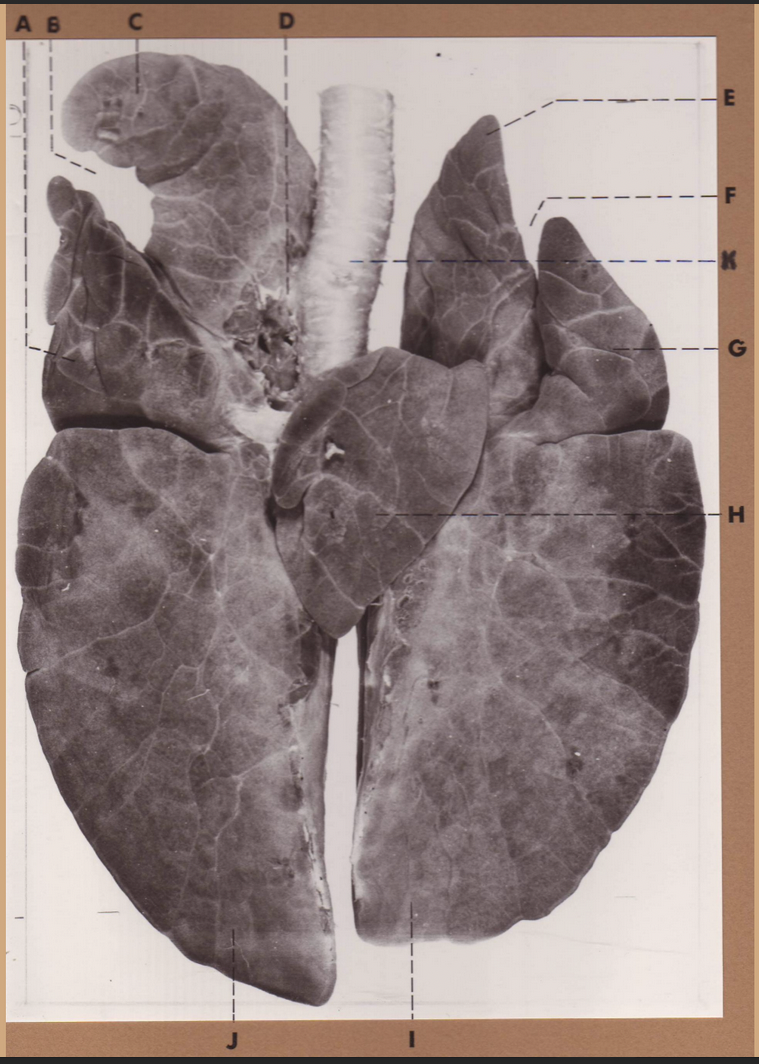

A

(dog lungs, dorsal)

L cranial lobe

B

(dog lungs, dorsal)

cranial segment, L cranial lobe

C

(dog lungs, dorsal)

caudal segment, L cranial lobe

D

(dog lungs, dorsal)

apex

E

(dog lungs, dorsal)

trachea

F

(dog lungs, dorsal)

R cranial lobe

G

(dog lungs, dorsal)

middle lobe

H

(dog lungs, dorsal)

R caudal lobe

I

(dog lungs, dorsal)

accessory lobe

J

(dog lungs, dorsal)

L caudal lobe